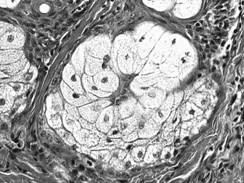

Microscopia electronica (fig. I.2.1) evidentiaza tot o celula polarizata, cu aceleasi caracteristici ale polului apical, ale polului bazal si a prezentei si distributiei jonctiunilor. RER este extrem de bine dezvoltat in zona bazala, iar complexul Golgi - supranuclear. Etapele de realizare a produsului de secretie sunt similare cu cele prezentate anterior la celula zimogena, cu diferenta ca aici are loc un intens proces de glicozilare sub actiunea unei glicozil-transferaze.

Procesul de glicozilare incepe in RER prin aditionarea de glucide, mai ales la extremitatile aminolaterale ale asparaginei, si se desavarseste in complexul Golgi, in special in zona trans. In cazul sintezei de glicoproteine sulfatate, adaugarea radicalilor sulfat are loc tot in complexul Golgi, sub actiunea unei sulfo-transferaze. Tot complexul Golgi este implicat si intr-un proces de concentrare, ce poate atinge pana la 25% din masa materialului sintetizat. Ulterior, ca si in cazul celulelor zimogene, se desprind vacuole mici care, prin coalescenta, vor genera vacuole secretoare mari - ce se traduc optic prin prezenta mucusului in cele doua treimi apicale ale celulei mucigene.

In raport cu natura produsului de secretie, adenomerele acinoase pot fi: seroase, mucoase sau mixte. In acinul seros (fig. I.2.12, fig. I.2.13) celulele secretoare sunt de tip zimogenic, iar lumenul este central, mic si stelat, datorita distantarii polurilor apicale ale celulelor secretoare, deasupra complexelor jonctionale apicale. Acest tip de acin apare in pancreasul exocrin, parotida (glanda salivara seroasa pura) si in glandele salivare mixte.

Acinul mucos (fig. I.2.14, fig. I.2.15) contine in exclusivitate celule de tip mucigen (cu pol inchis), a caror citoplasma apare palida. Lumenul acinului mucos este mai larg comparativ cu acinul seros, si aparent rotund. Acest tip de acin se gaseste in glandele salivare mixte si in glanda palatina (glanda salivara mucoasa pura).

Acinul mixt (fig. I.2.16, fig. I.2.17) este alcatuit majoritar din celule mucigene (in numar de 4-5) si din cateva celule seroase (in numar de 1-5) ce coafeaza de obicei, sub forma unei semilune - semiluna Gianuzzi, un pol al adenomerului. Acest tip de acin este caracteristic pentru glandele salivare mixte.